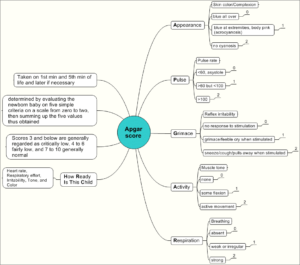

Maternal-Newborn Nursing

Cheatsheets

71

Mnemonics

24

Images

86

Picmonic

0